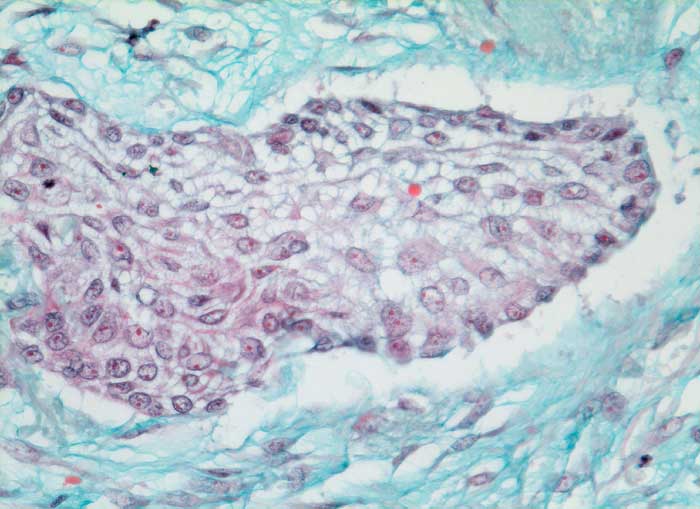

mässig differenziertes Plattenepithelkarzinom

Solider Tumorzellverband ohne erkennbare Verhornung. Die Desmosomen zwischen den Zellen sind sehr gut erkennbar. Reichlich desmoplastisches Stroma.

Histologie

Vergrösserung

320